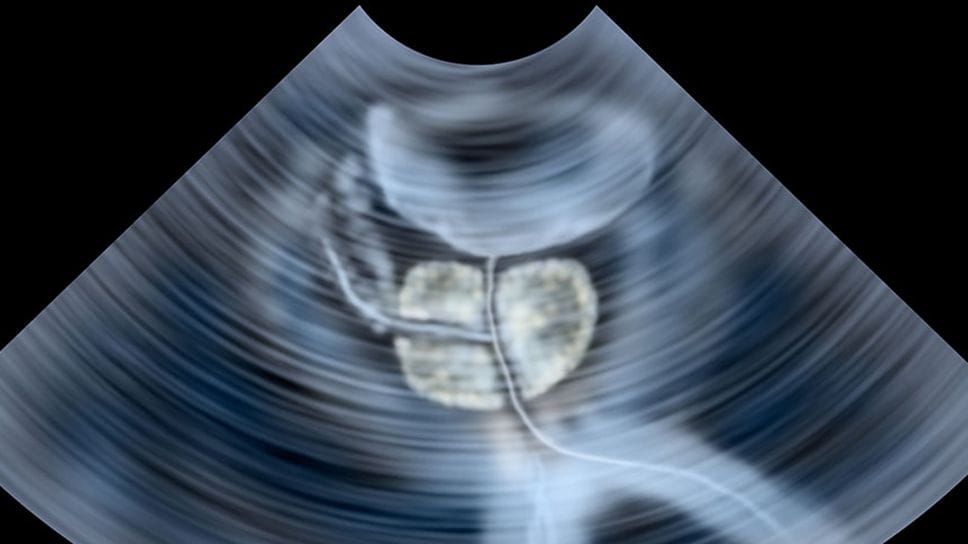

«L’iperplasia prostatica benigna, detta anche comunemente ipertrofia prostatica, è una condizione - come dice il nome - benigna (quindi non legata a tumori) caratterizzata dall’aumento progressivo del volume della prostata. La prostata è una ghiandola dell’apparato genito-urinario maschile situata immediatamente sotto la vescica e che circonda il primo tratto dell’uretra. Quando il tessuto prostatico aumenta di volume, può comprimere l’uretra, ostacolando il normale deflusso dell’urina».

«Il trattamento va sempre personalizzato. La scelta dipende dall’età del paziente, dal volume e dalla forma della prostata, dalla presenza di altre patologie e dalle aspettative personali. Nei casi lievi si può iniziare con una terapia farmacologica. Tuttavia, i farmaci non sempre sono sufficienti nel lungo periodo e possono avere effetti collaterali. Negli ultimi anni, però, abbiamo assistito a un grande sviluppo delle tecniche mini-invasive: si tratta di tecniche che hanno profondamente cambiato l’approccio all’iperplasia prostatica benigna, consentendo di ridurre l’ostruzione prostatica con minore trauma per il paziente. Alcune utilizzano tecnologie laser, altre sfruttano il vapore acqueo o dispositivi meccanici che allargano il canale uretrale. La caratteristica comune è quella di essere eseguite senza incisioni esterne, con minore sanguinamento, ricoveri più brevi e tempi di recupero decisamente più rapidi».